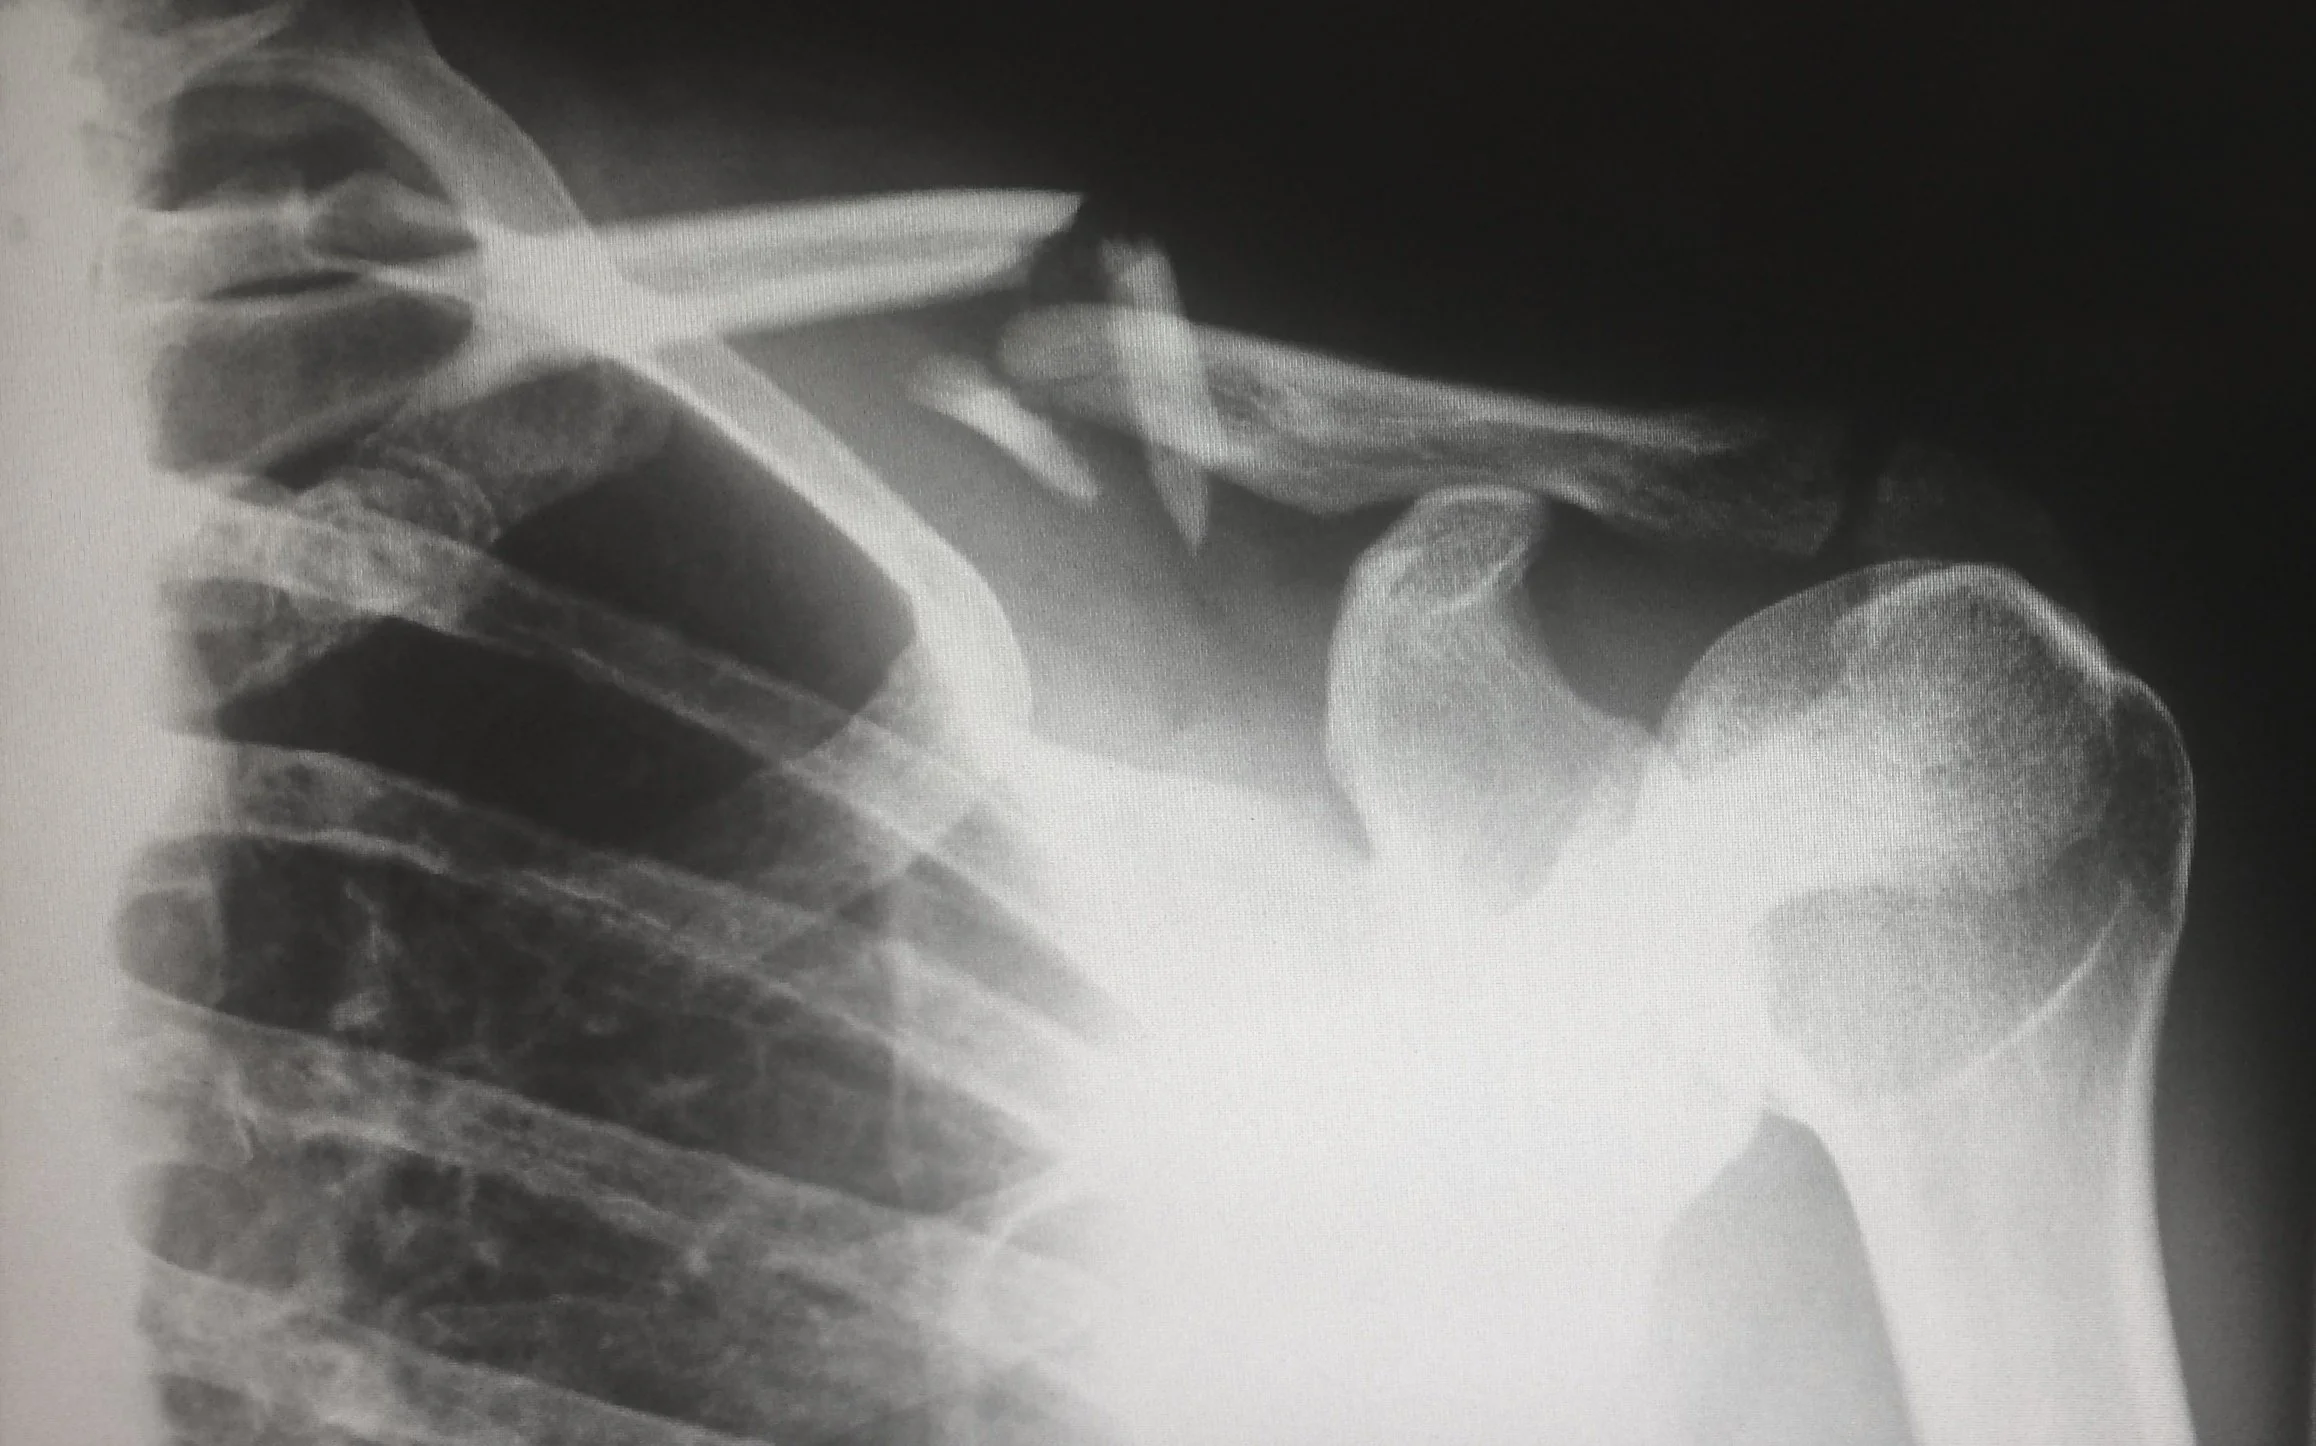

We have learned so many better ways of treating injuries since the 1970’s when Dr. Gabe Mirkin, MD first introduced R.I.C.E. theory. We have also learned through a multitude of studies that NSAIDs can delay healing of broken bones, damaged/ strained ligaments and tissue structures. The body needs the inflammatory process and angiogenesis for bone remodeling to occur. You will not speed healing long term by reducing blood flow. These will only prolong the healing process. However, in an acute injury where swelling is causing circulation or nerve compression issues, R.I.C.E., may be an appropriate modality until you can receive care from a medical provider.